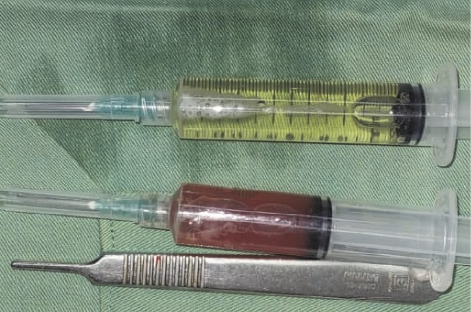

It was determined by anamnesis, physical examination, and imaging that the diagnosis was an ovarian cyst. As we continue laparotomy with midline incision from obstetrics department, we revealed a 8x8x10 cm sized cystic mass within the left transverse colon omentum, uterus and both ovaries were normal (Figure 3). We excised the cyst in toto and omentectomy then sent for pathological anatomy and cytology analysis. Instead of an ovarian cyst, we found an omental cyst during the operation (Figure 4), thus we had to conduct an excision and omentectomy and postoperatively achieved favorable results. Pathological examination revealed findings a inclusion cyst containing connective tissue, fat, and muscle. Cytology findings are suggestive for transudative effusion from the cyst and the international system for reporting serous fluid (ascites) cytopathology negative for malignancy (Figure 5). She was discharged three day after.

Figure 5. Serous fluid aspirated from cyst and serosanguinous fluid from intra-peritoneal